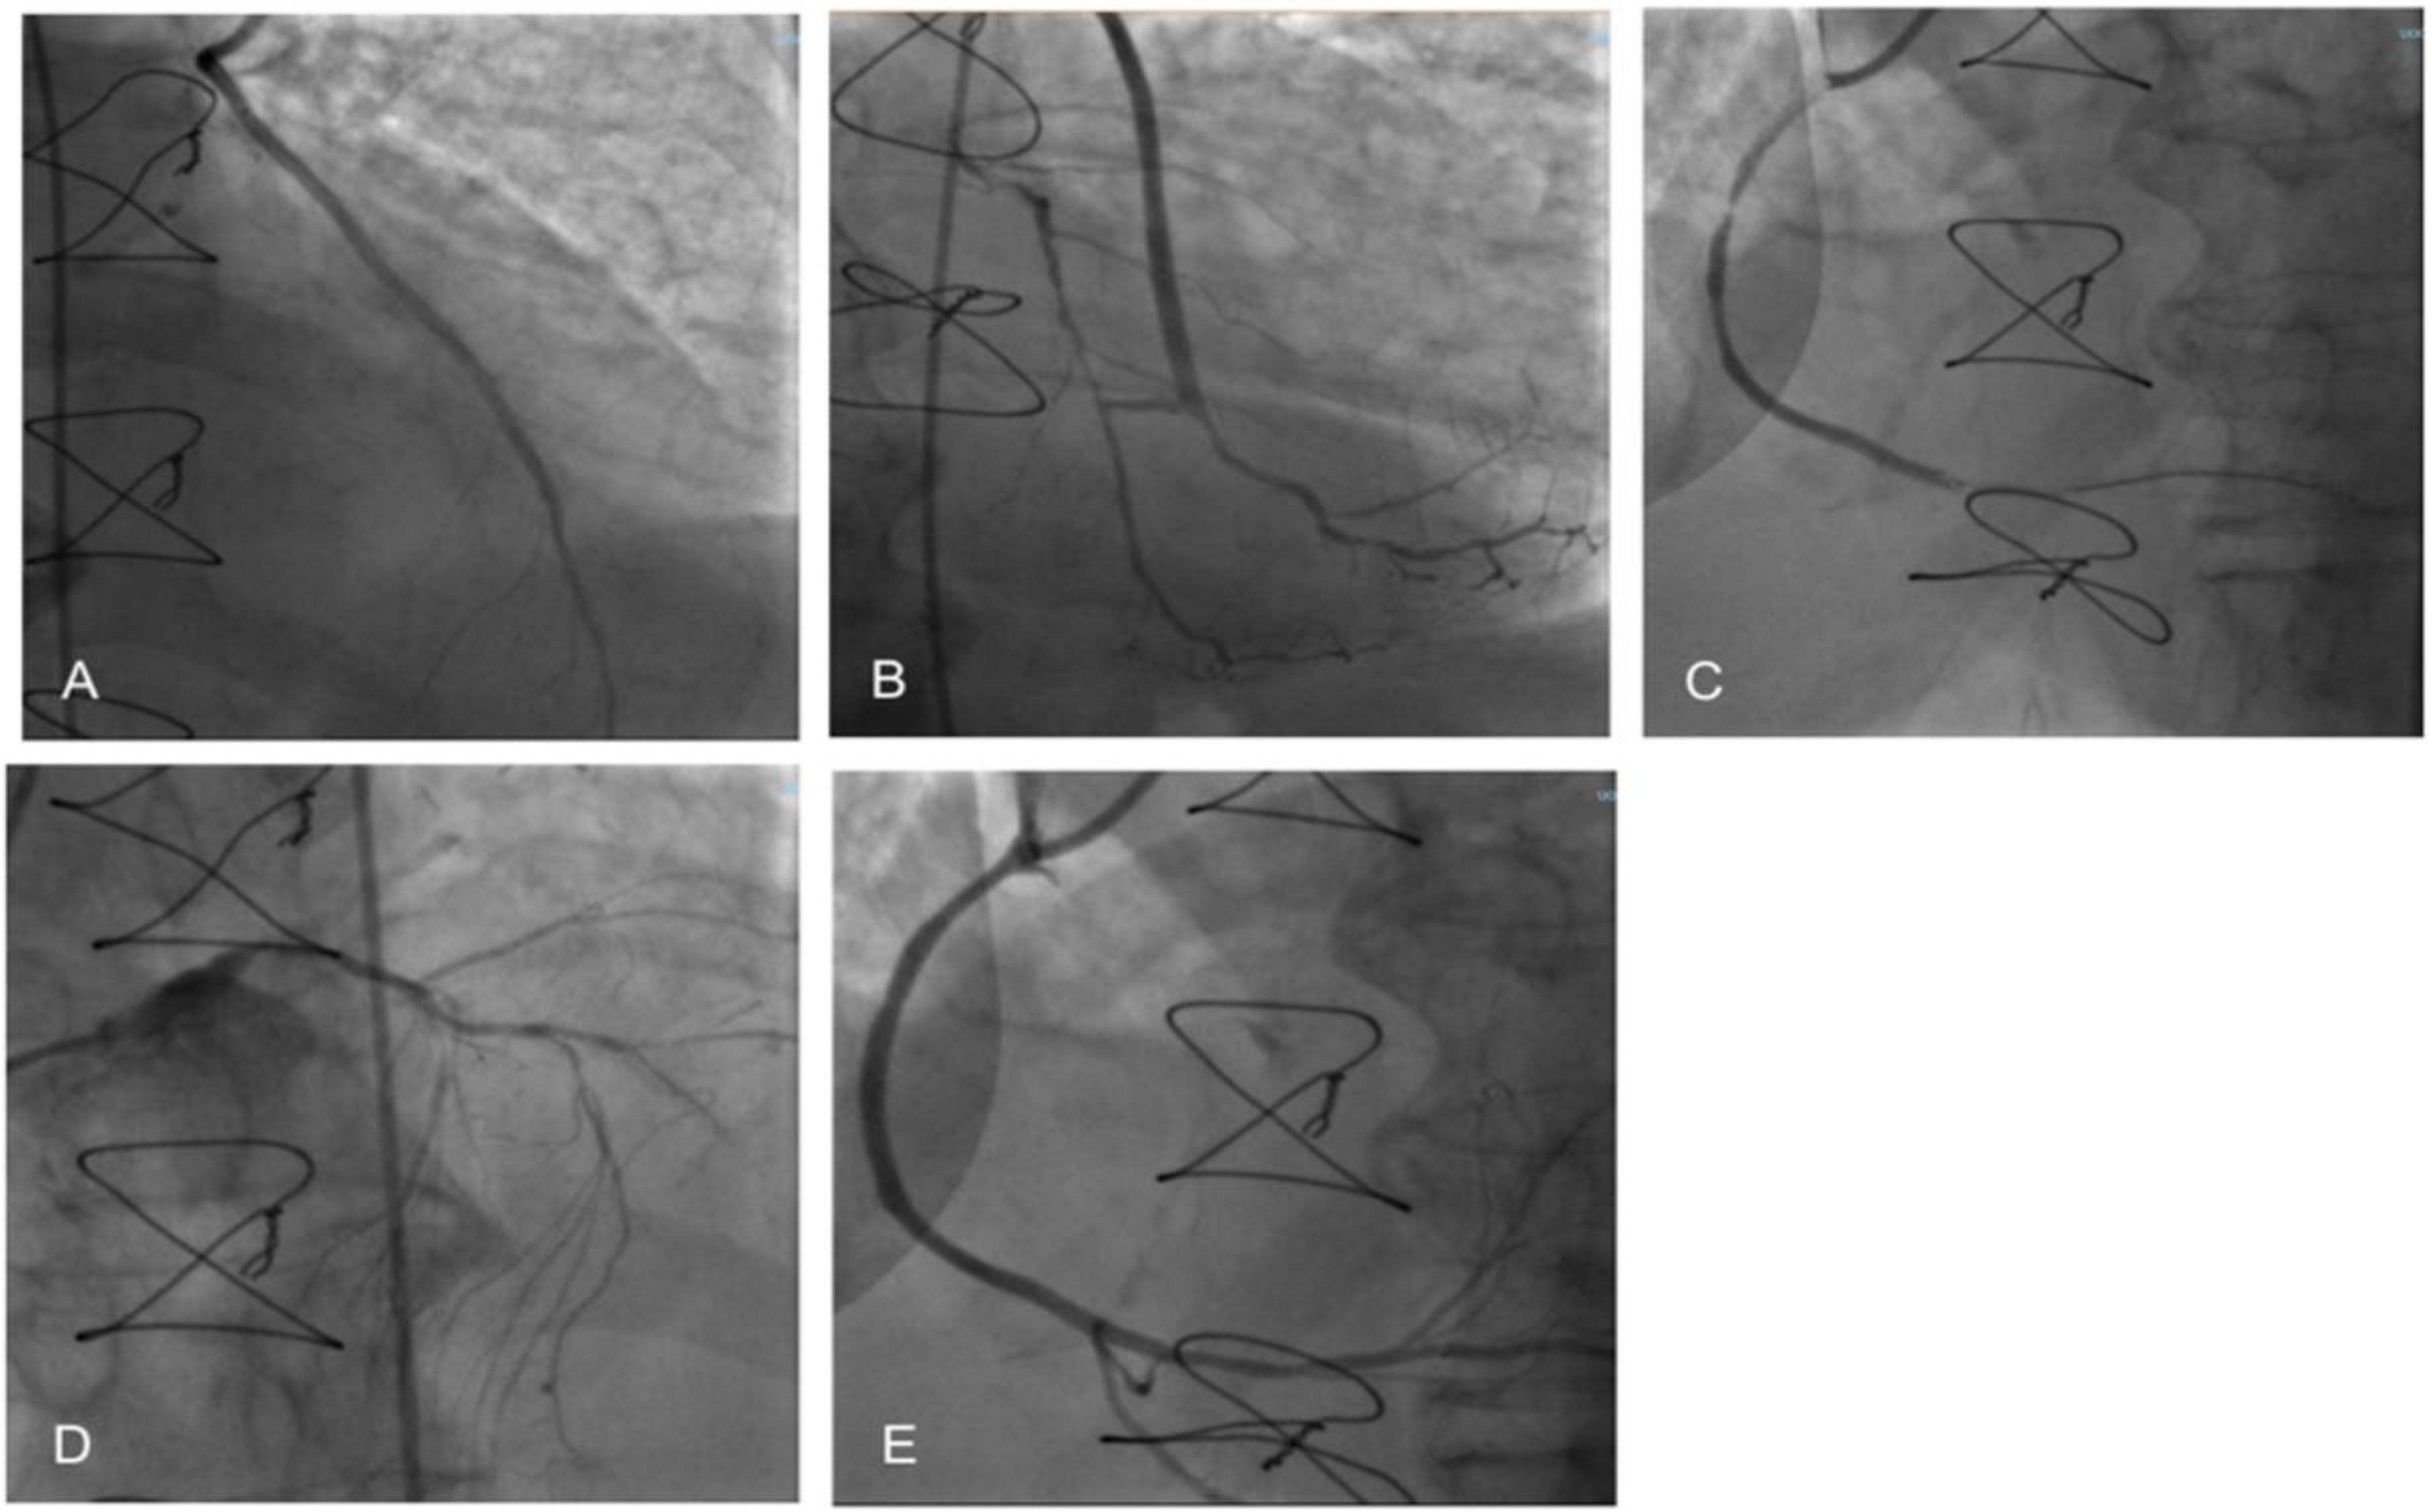

2. Case Report